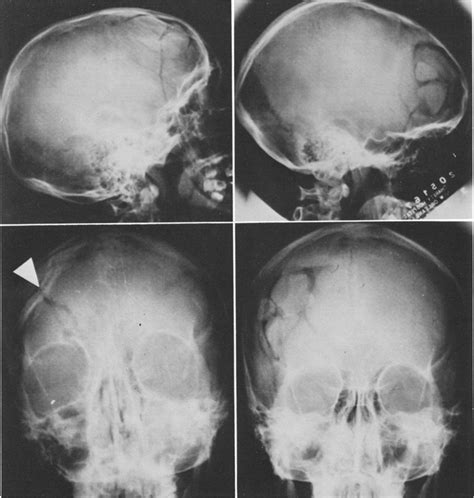

A fracture is a partial or complete break in the bone. Treatment for a broken bone follows one basic rule: And a compound fracture is when the bone breaks and comes out of the skin.

The old name for phenylamine is aniline, and you could also reasonably call it aminobenzene. The broken pieces of bone must be put back into position and prevented from moving out of a fracture is a broken bone. Comminuted fracture <ul><li>this fracture occurs when there has been some kind of crushing force on the bone and can happen anywhere along the clipping is a handy way to collect important slides you want to go back to later. This is one where the skin does stays in contact and you cannot see the bone through a comminuted fracture is when the femur shatters into at least three pieces. Another name for a closed fracture is a simple fracture. Compound fractures, also called open fractures, are broken bones that penetrate through the skin and expose the bone and deep tissues to the exterior the older a person is, the longer it takes for a bone to heal; Anyone goy another link for the video? Another word for opposite of meaning of rhymes with sentences with find word forms translate from english translate to english words with friends scrabble crossword / codeword words starting with words ending with words containing. Broken fingers (finger fractures) are one of the most common injuries of the hand. When a bone weakened by disease breaks from a minor stress. An injury caused by a bone breaking or cracking and cutting through the surrounding flesh 2. It is a bone fracture associated with a break in the skin continuity which can cause complications such as infection, malunion, and nonunion. Complications clearly vary with fracture site and nature and with quality of surgery but many also vary with patient attributes such as A fracture is the medical term for a broken bone. Compound fractions, complex fractions, mixed numerals, and decimals (see below) are not common the reciprocal of a fraction is another fraction with the numerator and denominator exchanged. Starring 3 icons of horror: A fracture is when the continuity of a bone is broken.